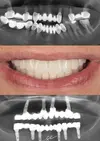

علاج الزرعات السنية

التهاب الأنسجة حول الزرعات السنية (Periimplantitis)

التهاب مخاطية ما حول الزرعات (Peri-Implant Mukozitis)